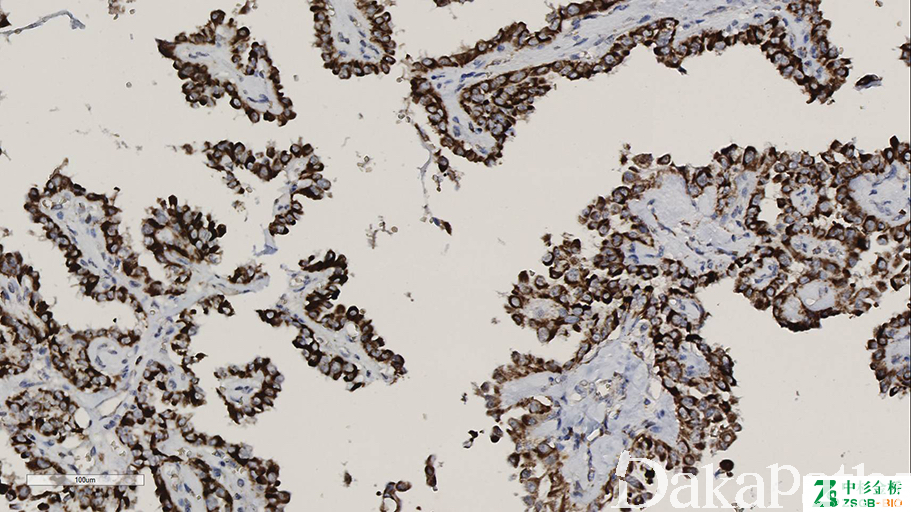

BRAF-V600E

BRAF 基因定位位于 7q34,是下游 MAPK 信号传导通路最强的激活剂,其主要突变位点即密码子 600 的突变(V600E)。在毛细胞白血病中突变率达 90%以上,另外还在多种肿瘤组织中发现 BRAF V600E 突变,如恶性黑色素瘤、甲状腺乳头状癌、结直肠癌、多形性黄色星形细胞瘤、毛细胞型星型细胞瘤、朗格罕细胞组织细胞增生症、卵巢交界性肿瘤、胶质瘤等。

信号定位: 胞浆

经常阳性(<75%,≥55%的病例阳性): 甲状腺乳头状癌、甲状腺腺瘤、卵巢浆液性交界性肿瘤/非典型增生性浆液性肿瘤